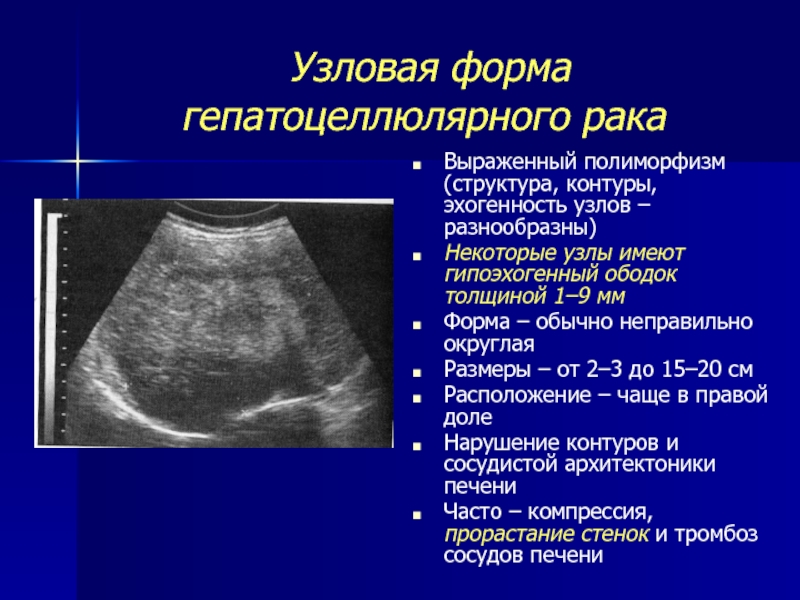

Метастатические поражения печени в ультразвуковом изображении характеризуются